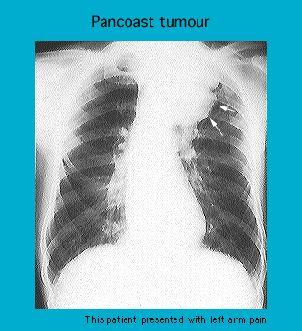

Radiograph showing a Pancoast tumour